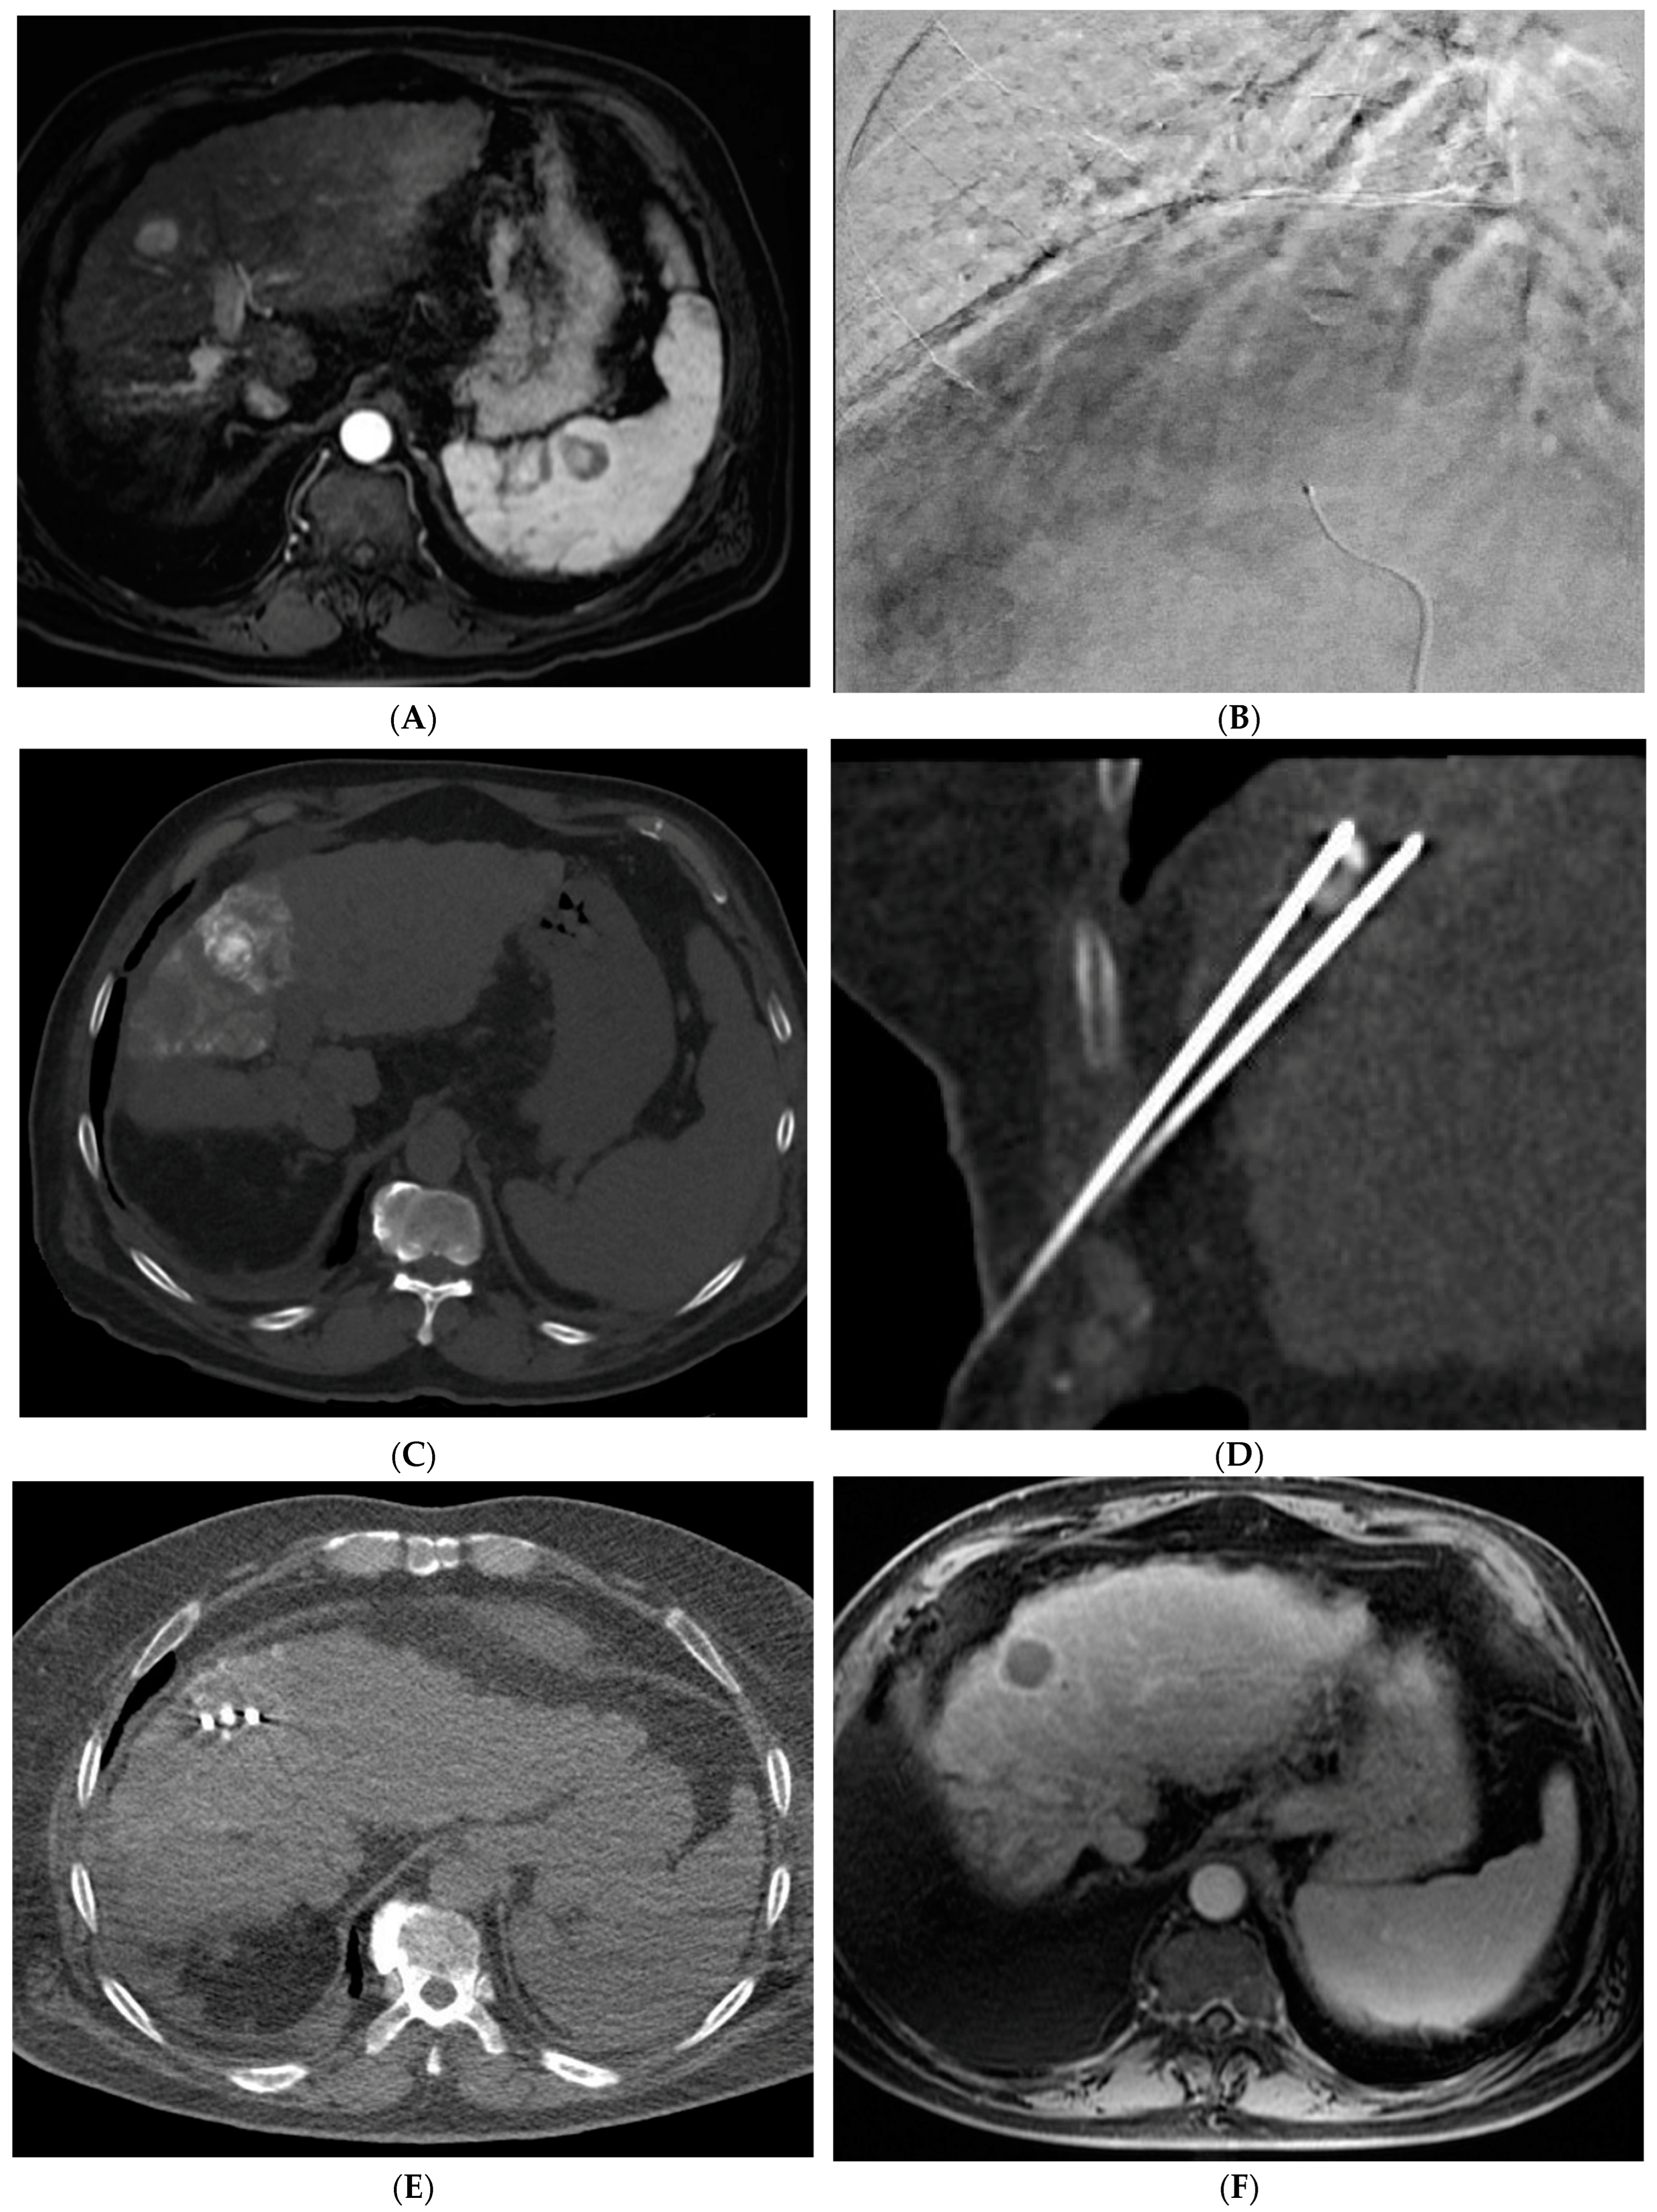

Figure 2. 88-year-old woman with HCC on a background of cirrhosis secondary to autoimmune hepatitis treated with conventional TACE. (A) Arterial phase MRI showing a 2.2 cm arterially enhancing lesion in hepatic segment 8. (B) Delayed phase MRI showing washout of the lesion. (C) Intraprocedural CTA demonstrating supply to the hypervascular lesion from the segment 8 arterial branch. (D) Post procedure non-contrast CT demonstrating the ethiodized oil deposition within the tumor and surrounding segment 8 parenchyma. (E) Follow up arterial phase MRI one month after treatment demonstrating no arterial enhancement within the treated lesion consistent with complete response.

2.2. Transarterial Chemoembolization (TACE)

TACE is the mainstay of treatment in intermediate stage (BCLC-B) HCC. Conventional TACE (cTACE) is performed with a combination of ethiodized oil and chemotherapy, in the US most commonly doxorubicin, either alone or in combination with mitomycin and cisplatin, followed by an embolic agent such as polyvinyl alcohol (PVA) or a gelatin sponge (Figure 2). TACE with drug-eluting beads (DEB-TACE) uses doxorubicin-loaded microspheres as a simultaneous drug-delivery and embolic agent. In the PRECISION V trial, the two techniques were compared, and results demonstrated a decrease in systemic side effects with DEB-TACE with similar survival rates [27]. Another study by Li et al. similarly showed a decrease in complications and prolonged interval between treatments with DEB-TACE [28]. In a more recent study, the PRESIDENT trial, cTACE was again compared to the more modern techniques of DEB-TACE [29]. The results demonstrated that the cTACE cohort had higher rates of complete response at 1- and 3-month time points (84.2%, 75.2%) versus the DEB-TACE group (35.7%, 27.6%). However, the cTACE group had significantly higher rates of adverse events attributed to post embolization syndrome including fever, fatigue, malaise, abdominal pain, anorexia, and lab abnormalities including elevated bilirubin, AST, ALT, and hypoalbuminemia [29].

The combination of locoregional therapies is also an area of interest. In a meta-analysis, the combination of TACE and RFA compared to surgical resection showed no difference in overall survival but reduced complications in the combination therapy group [65]. The ethiodized oil retention within HCC following cTACE can also be used as a marker to guide percutaneous ablation (Figure 4). Stereotactic body radiotherapy (SBRT) is currently being studied in combination with TACE with promising results. In a propensity-scored matched analysis by Wong et al., patients who received the combination of SBRT + TACE had significantly higher one- and three-year overall survival and improved radiological disease control [66]. There is also interest in using SBRT in cases of local relapse following TACE. A phase III trial was closed early due to slow accrual, but results showed superior local control of SBRT versus repeat TAE/TACE [67]. SBRT remains a promising non-invasive treatment for unresectable HCC. Further research is needed to define its role within the HCC treatment paradigm.